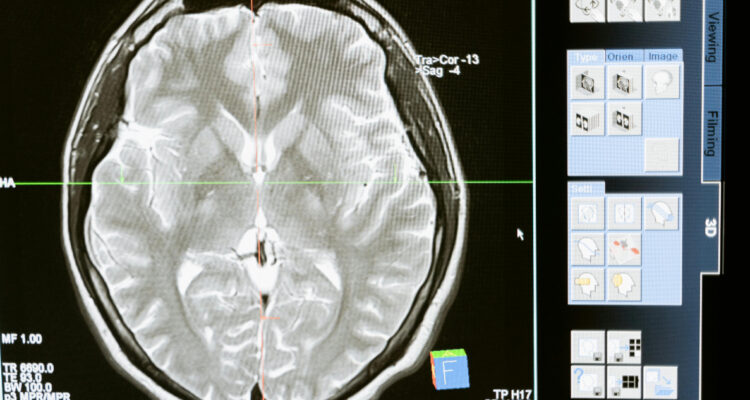

Para mapear este envejecimiento, los científicos utilizaron modelos de aprendizaje automático entrenados con escáneres cerebrales obtenidos del Biobanco del Reino Unido de 15.334 participantes sanos, para medir la diferencia entre la edad cerebral predicha de un individuo y su edad real, conocida como brecha de edad cerebral.

Este modelo se utilizó posteriormente para analizar dos resonancias magnéticas cerebrales de 996 participantes sanos, tomadas con al menos dos años de diferencia. En el grupo control (564 individuos), ambos escáneres se realizaron antes de la pandemia, y en el grupo “pandemia” (432 individuos), un escáner se realizó antes y otro después del inicio de la misma.